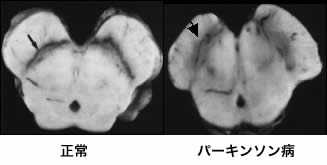

- 身体的変化: PD の運動症状を引き起こす脳の変化も疲労の一因となる可能性がありますが、PD 症状の重症度は疲労の重症度に関連しない可能性があります。